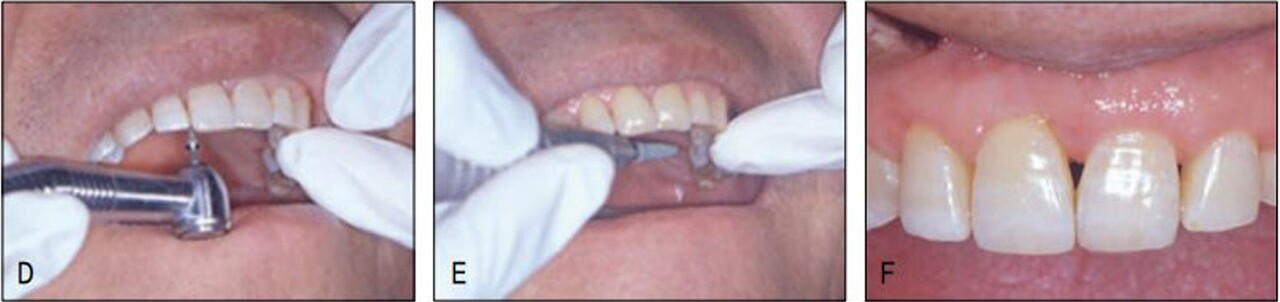

가철식 장치이어서 다소의 경사이동이 발생하였고 치주질 환으로 우측의 중절치가 더 정출하여 비심미적인 절단연이었으나 스트리핑 그리고 re-shaping 등을 이용하여 심미적인 절단연을 만들어주었다. 교정을 주저하였던 환자는 설측 및 투명장 치 등 심미적 장치로 인해 교정치료 내내 크게 만족해 하였다(그림 23-7~10).